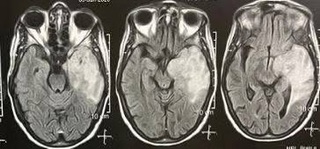

بدأ الفريق الطبي الأسبوع بإنقاذ حياة مريض يبلغ من العمر 83 عامًا، كان يعاني من نزيف حاد بالمخ نتيجة ارتفاع ضغط الدم. بفضل الاستجابة السريعة، تم تجهيز المريض وإجراء عملية تفريغ النزيف خلال 30 دقيقة فقط، تلتها متابعة دقيقة في العناية المركزة.